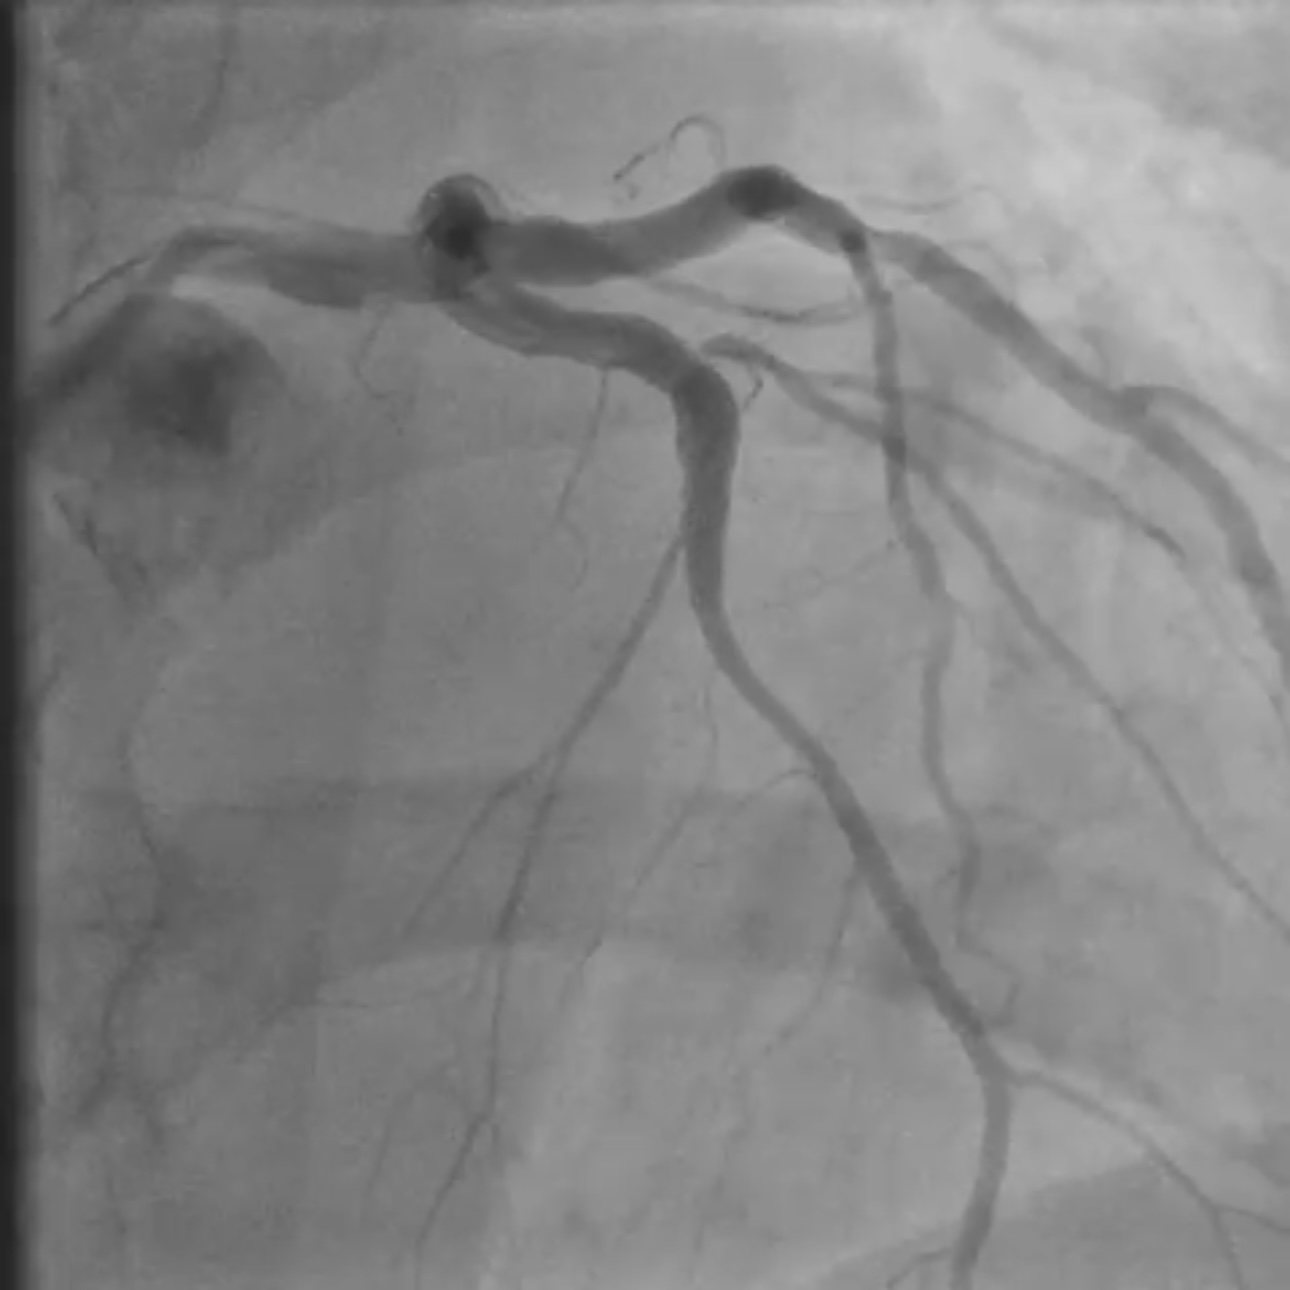

Coronary angiography revealed two critical stenoses in the mid–left anterior descending (LAD) artery separated by a short fusiform aneurysmal segment. A diagonal branch originated near the proximal aneurysm margin. Implanting a covered stent was avoided due to the high risk of diagonal branch occlusion, and a drug-eluting balloon (DEB) strategy was rejected because it offered no vessel scaffolding and could destabilize the aneurysmal wall. A dual drug-eluting stent (DES) bridging technique was selected to stabilize the aneurysmal segment while maintaining branch perfusion. The procedure was performed via right radial access using a 6F XB guide catheter for enhanced support. A floppy guidewire was advanced into the distal LAD. Lesion preparation was performed with a 2.5 mm semi-compliant balloon. A 3.0 ¡¿ 15 mm DES was first deployed distally to treat the distal stenosis and establish a stable anchoring platform on healthy vessel. A second DES (3.5 ¡¿ 22 mm) was then implanted across the aneurysmal segment, with distal overlap onto the first stent to secure the construct outside the aneurysm. The proximal landing zone was carefully positioned in healthy vessel proximal to the aneurysm. Post-dilatation was deliberately limited to the landing zones with a non-compliant balloon to minimize mechanical stress on the aneurysmal wall. Final angiography showed optimal stent expansion, preserved flow to the diagonal branch, no dissection or perforation, and TIMI 3 flow. The patient received unfractionated heparin during PCI and dual antiplatelet therapy (aspirin + ticagrelor) per ACS guidelines.

Case Summary